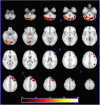

Expanding behavioral and neurobiological evidence affirms benefits of shared (especially parent-child) reading on cognitive development during early childhood. However, the majority of this evidence involves factors under caregiver control, the influence of those intrinsic to the child, such as interest or engagement in reading, largely indirect or unclear. The cerebellum is increasingly recognized as playing a "smoothing" role in higher-level cognitive processing and learning, via feedback loops with language, limbic and association cortices. We utilized functional MRI to explore the relationship between child engagement during a mother-child reading observation and neural activation and connectivity during a story listening task, in a sample of 4-year old girls. Children exhibiting greater interest and engagement in the narrative showed increased activation in right-sided cerebellar association areas during the task, and greater functional connectivity between this activation cluster and language and executive function areas. Our findings suggest a potential cerebellar "boost" mechanism responsive to child engagement level that may contribute to emergent literacy development during early childhood, and synergy between caregiver and child factors during story sharing.